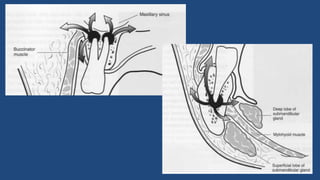

Fatores Determinantes da Localização

do Abscesso

• Relação do ápice com a cortical óssea

– Vestibular

– Palatino/Lingual

• Relação do ápice com as inserções musculares

– Vestíbulo bucal

– Espaços fasciais

Disseminação dos Abscessos na Maxila

Disseminação dos Abscessos na

Mandíbula

Espaços Fasciais e Disseminação das

Infecções

• Espaços virtuais

limitados pelas fáscias

musculares,

geralmente

preenchidos por

gordura, que facilitam a

disseminação das

odontogênicas

Fatores Determinantes daLocalização do Abscesso • Relação do ápice com a cortical óssea – Vestibular – Palatino/Lingual • Relação do ápice com as inserções musculares – Vestíbulo bucal – Espaços fasciais

Espaços Fasciais eDisseminação das Infecções • Espaços virtuais limitados pelas fáscias musculares, geralmente preenchidos por gordura, que facilitam a disseminação das infecções odontogênicas